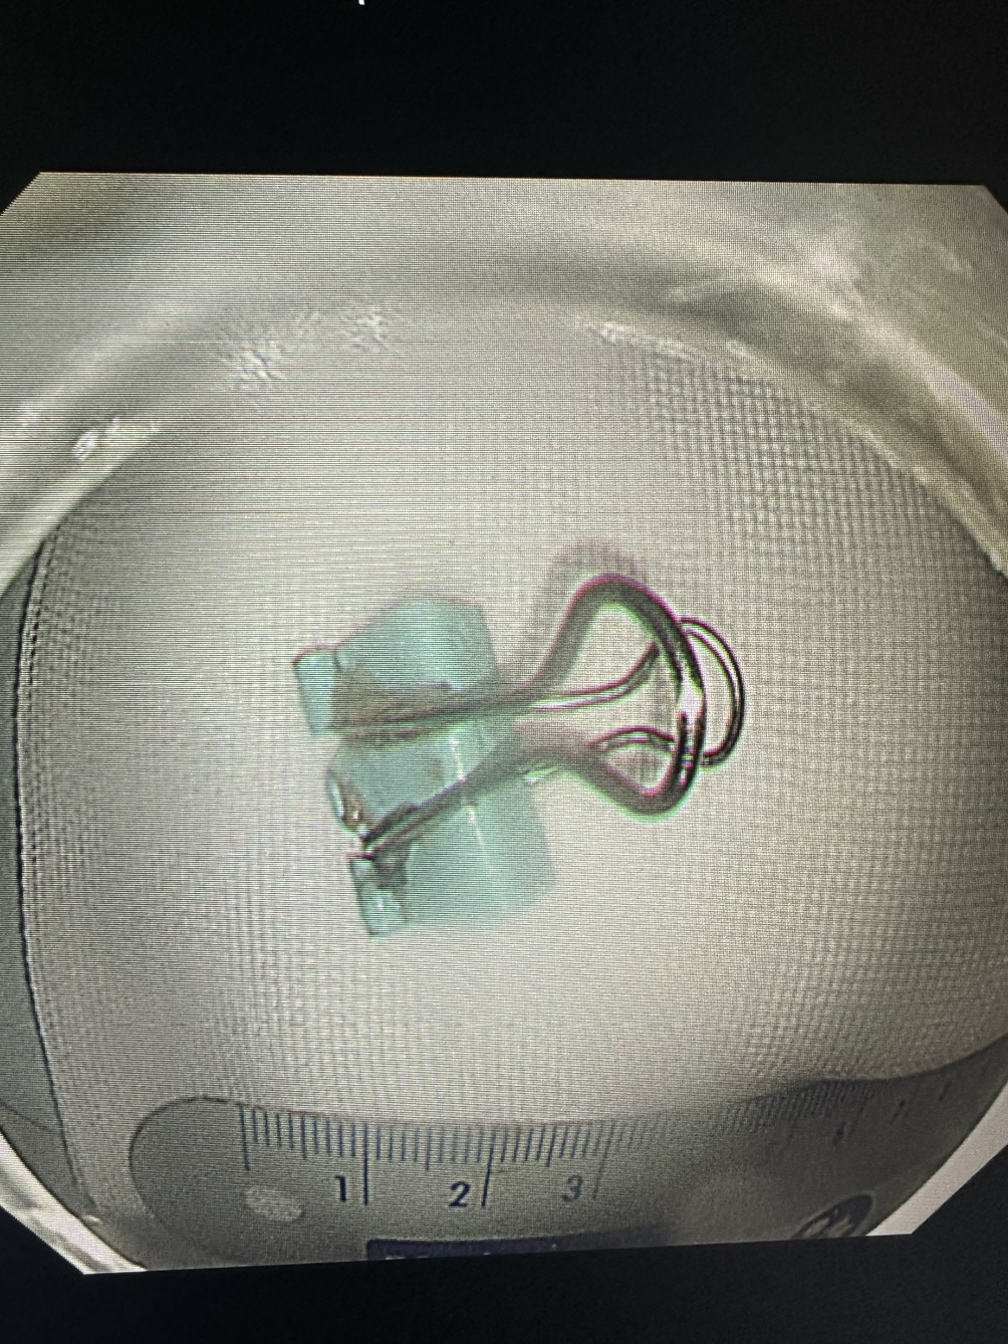

술을 먹고 실수로 삼키고, 약을 껍질채 삼키기도 한다. 이어폰을 삼키고 사탕 막대와 집게도 삼킨다. 기도가 아닌 식도로 들어가서 망정이지 틀니나 치아는 조심해야 한다. 이렇게나 대한민국 국민들은 다채롭게 삼키는구나.